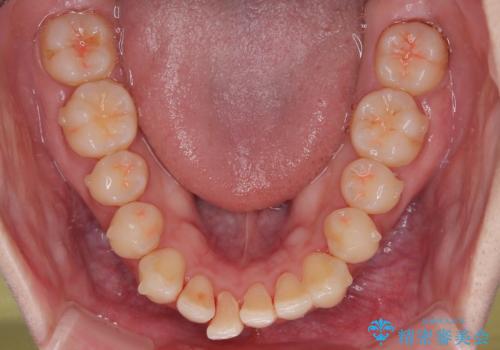

- 今回は「下の前歯のデコボコを治したい」と来院された患者様の症例をご紹介します。

診察してみると、下の前歯が並ぶためのスペースが足りないことが、歯並びがデコボコしている原因でした。

下の前歯の歯と歯の間をわずかに削ってスペースを作る(IPR)

奥歯を後ろに動かして、前歯が並ぶためのスペースを確保する

この計画により、デコボコだった下の前歯はしっかりと並び、わずか1年で治療を終えることができました